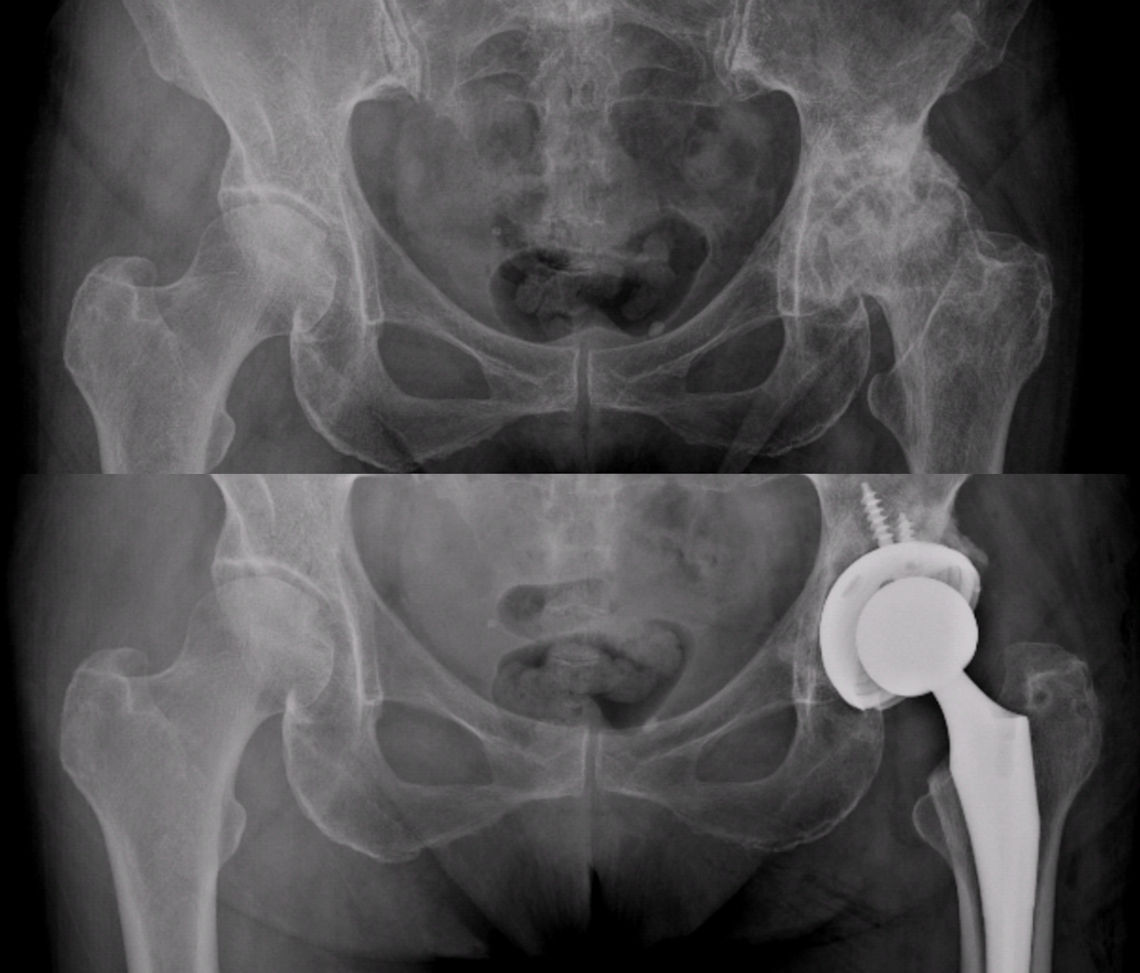

Ameliyatın ertesi gününde, aktif ve yardımlı kalça hareketlerine bir fizyoterapist gözetiminde başlanır. Merdiven çıkma, koltuğa oturma, yerden bir cisim alma gibi eğitimler verilir. Eğer dren yerleştirilmişse, ikinci gün çıkartılır ve röntgen kontrolünüz yapılır. Bacak kas kontrolünü kazanana kadar bir yürüteç veya koltuk değneği kullanılması, düşme riskini azaltmak için önemlidir. Röntgen çekilerek protezinizin son hali görüntülenir (Resim 6).

Resim 6: Sol kalçasında ileri evre aşınma ve yıpranma olan hastanın ameliyat öncesi ve sonrası röntgen görüntüleri.